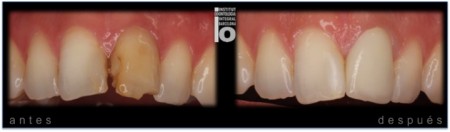

ESTÉTICA REPARACIÓN DE FRACTURA CON COMPOSITE

ESTÉTICA CON COMPOSITE.